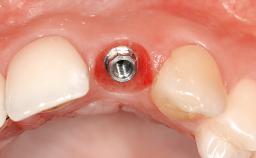

| Placement Protocol | - |

| Tooth Site | - |

| Socket Morphology | - |

| Socket Integrity | - |

| Bone Volume | - |